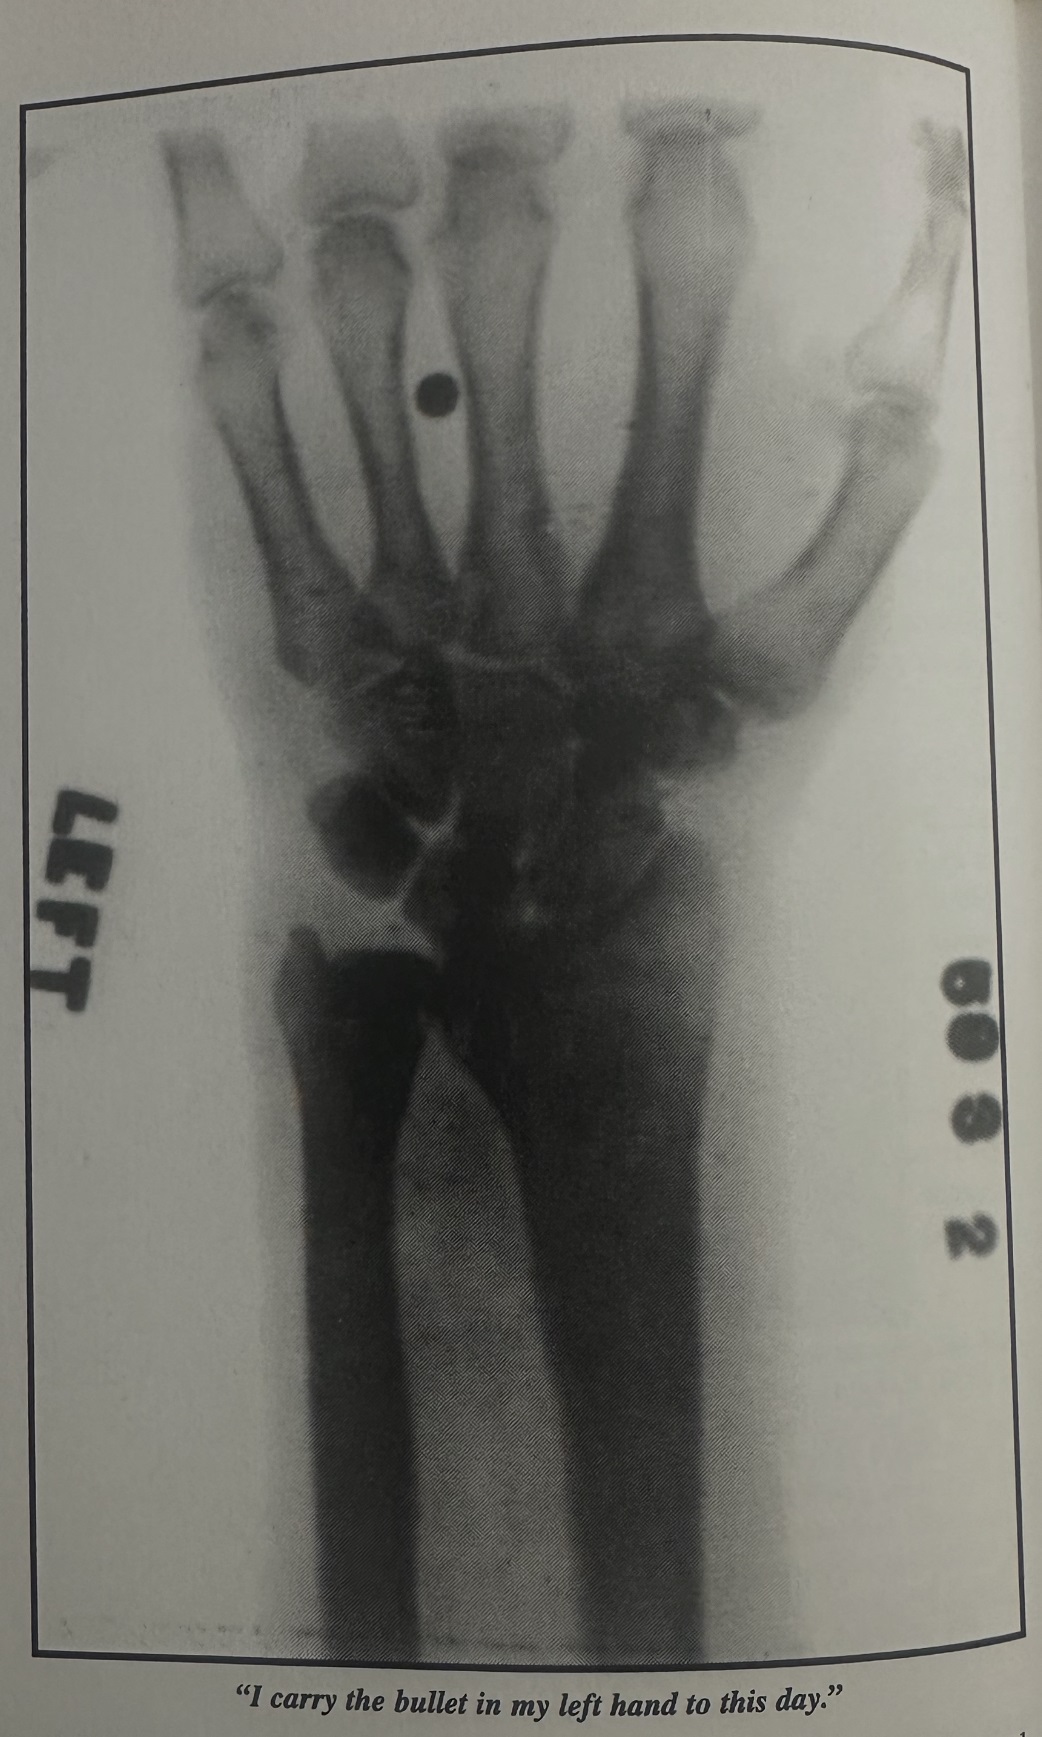

Prior to this photo with Arbuckle, Houdini risked his life and sustained injury making “The Grim Game”. So Houdini is showing off even with a cast on his left wrist he injured while making The Grim Game.